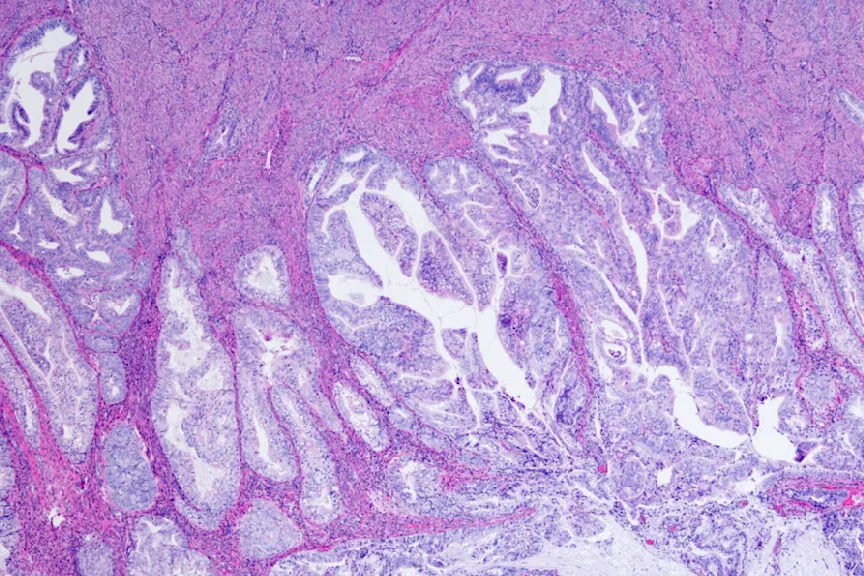

您的妇科医生将检查您并提出有关您的出血的问题,以确定活检是否合适。在活组织检查期间,Levine博士说,您的医生将从子宫内侧采用组织样本,其中一个看起来像稻草的小型设备。他说,病理学家将在显微镜下看看组织,并确认您是否患有癌症,前癌症或非癌症出血的出血。